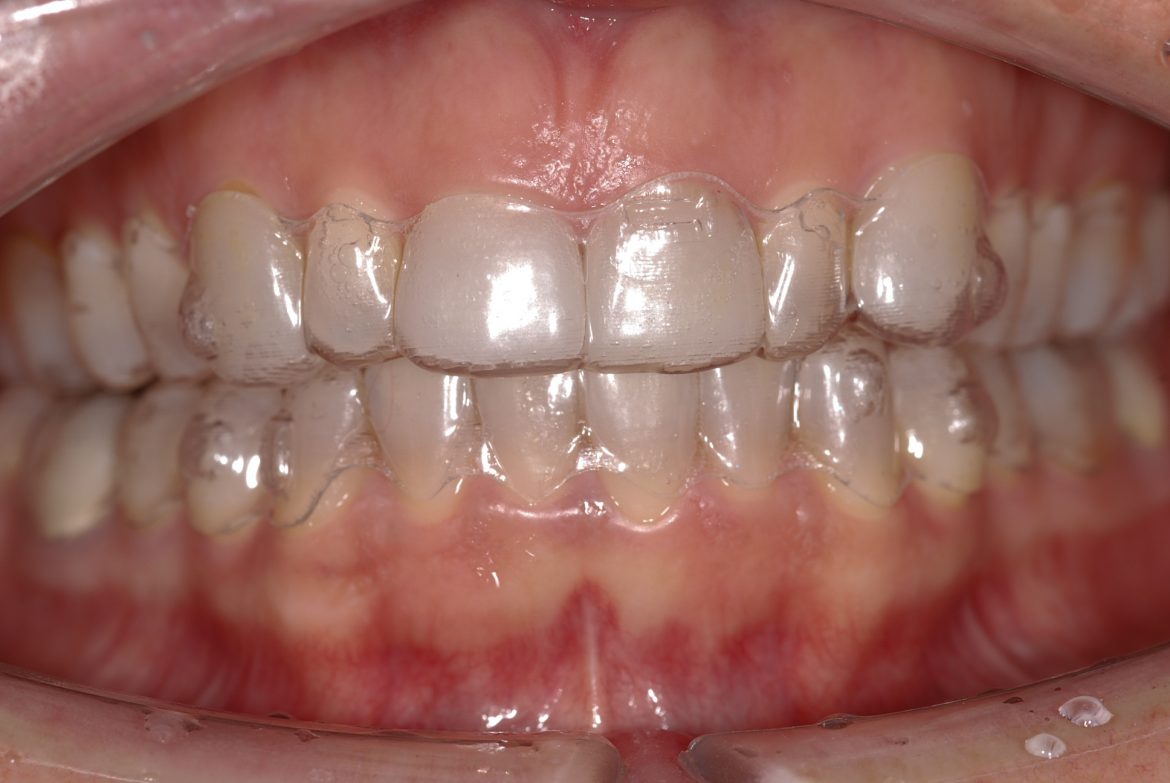

S-a utilizat sistemul Invisalign® (fig. 2) pentru a rezolva discrepanţa Bolton, prin lărgirea arcadei superioare şi inferioare. Aceasta conduce la diasteme incisive superioare, care ar evidenţia iniţial microdonţia incisivilor laterali, dar care ulterior s-ar putea restaura cu faţete din porţelan.

S-a obţinut un wax-up de laborator ca şi bază a mock-up-ului, care s-a realizat pentru a stabili şi a studia estetica finală a zâmbetului pacientului. După efectuarea modificărilor pe mock-up în consultaţie cu pacientul, s-a fabricat un ghid chirurgical care să indice inciziile chirurgicale ce urmau a fi efectuate de parodontolog în cursul intervenţiei chirurgicale.